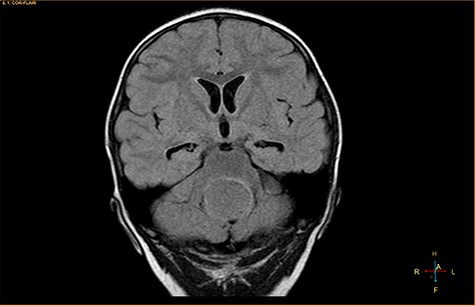

A 3-year-old male, who suffered from a sudden, tonic–clonic seizure, followed by a short period of unconsciousness, was instantly transported to Children’s Hospital 2. The patient’s medical history was normal. No neurological deficits were detected during the clinical assessment, and laboratory tests and electroencephalography were within acceptable ranges. The clinician performed a brain magnetic resonance imaging (MRI) scan, with contrast agent. No lesions were recognized in the supratentorial structures. A clear boundary cystic mass (27 × 25 × 26 mm3) was located in the medulla oblongata, without perilesional vasogenic edema. Hydrocephalus was not observed. The signal intensity of the mass was low on the sagittal T1-weighted image (Fig. 1) and high on the axial T2-weighted image (Fig. 2). On coronal fluid-attenuated inversion recovery imaging, the mass was isointense relative to the parenchyma, but the intensity was higher than that of cerebrospinal fluid (CSF, Fig. 3). On susceptibility-weighted imaging, no indicators of hemorrhage or ossification were observed within the mass. The mass was partially hyperintense on diffusion-weighted imaging (DWI) and slightly hypointense on the apparent diffusion coefficient (ADC) map. The mean ADC values of the parenchyma, mass and CSF were 0.71, 1.3 and 1.59 × 10−3 mm2/s, respectively (Fig. 4). On T1-weighted imaging, with contrast enhancement, the thin wall of the mass was very slightly enhanced, and we observed a tiny nodule inside the mass that was strongly enhanced (Fig. 5). With a provisional diagnosis of pilocytic astrocytoma, the patient underwent surgery to completely eradicate the tumor. Eventually, the histopathological result revealed a typical EC (Fig. 6). The postoperative period was uneventful, and the patient was discharged after 2 weeks.

Coronal fluid-attenuated inversion recovery image, showing an isointense mass relative to the surrounding parenchyma.